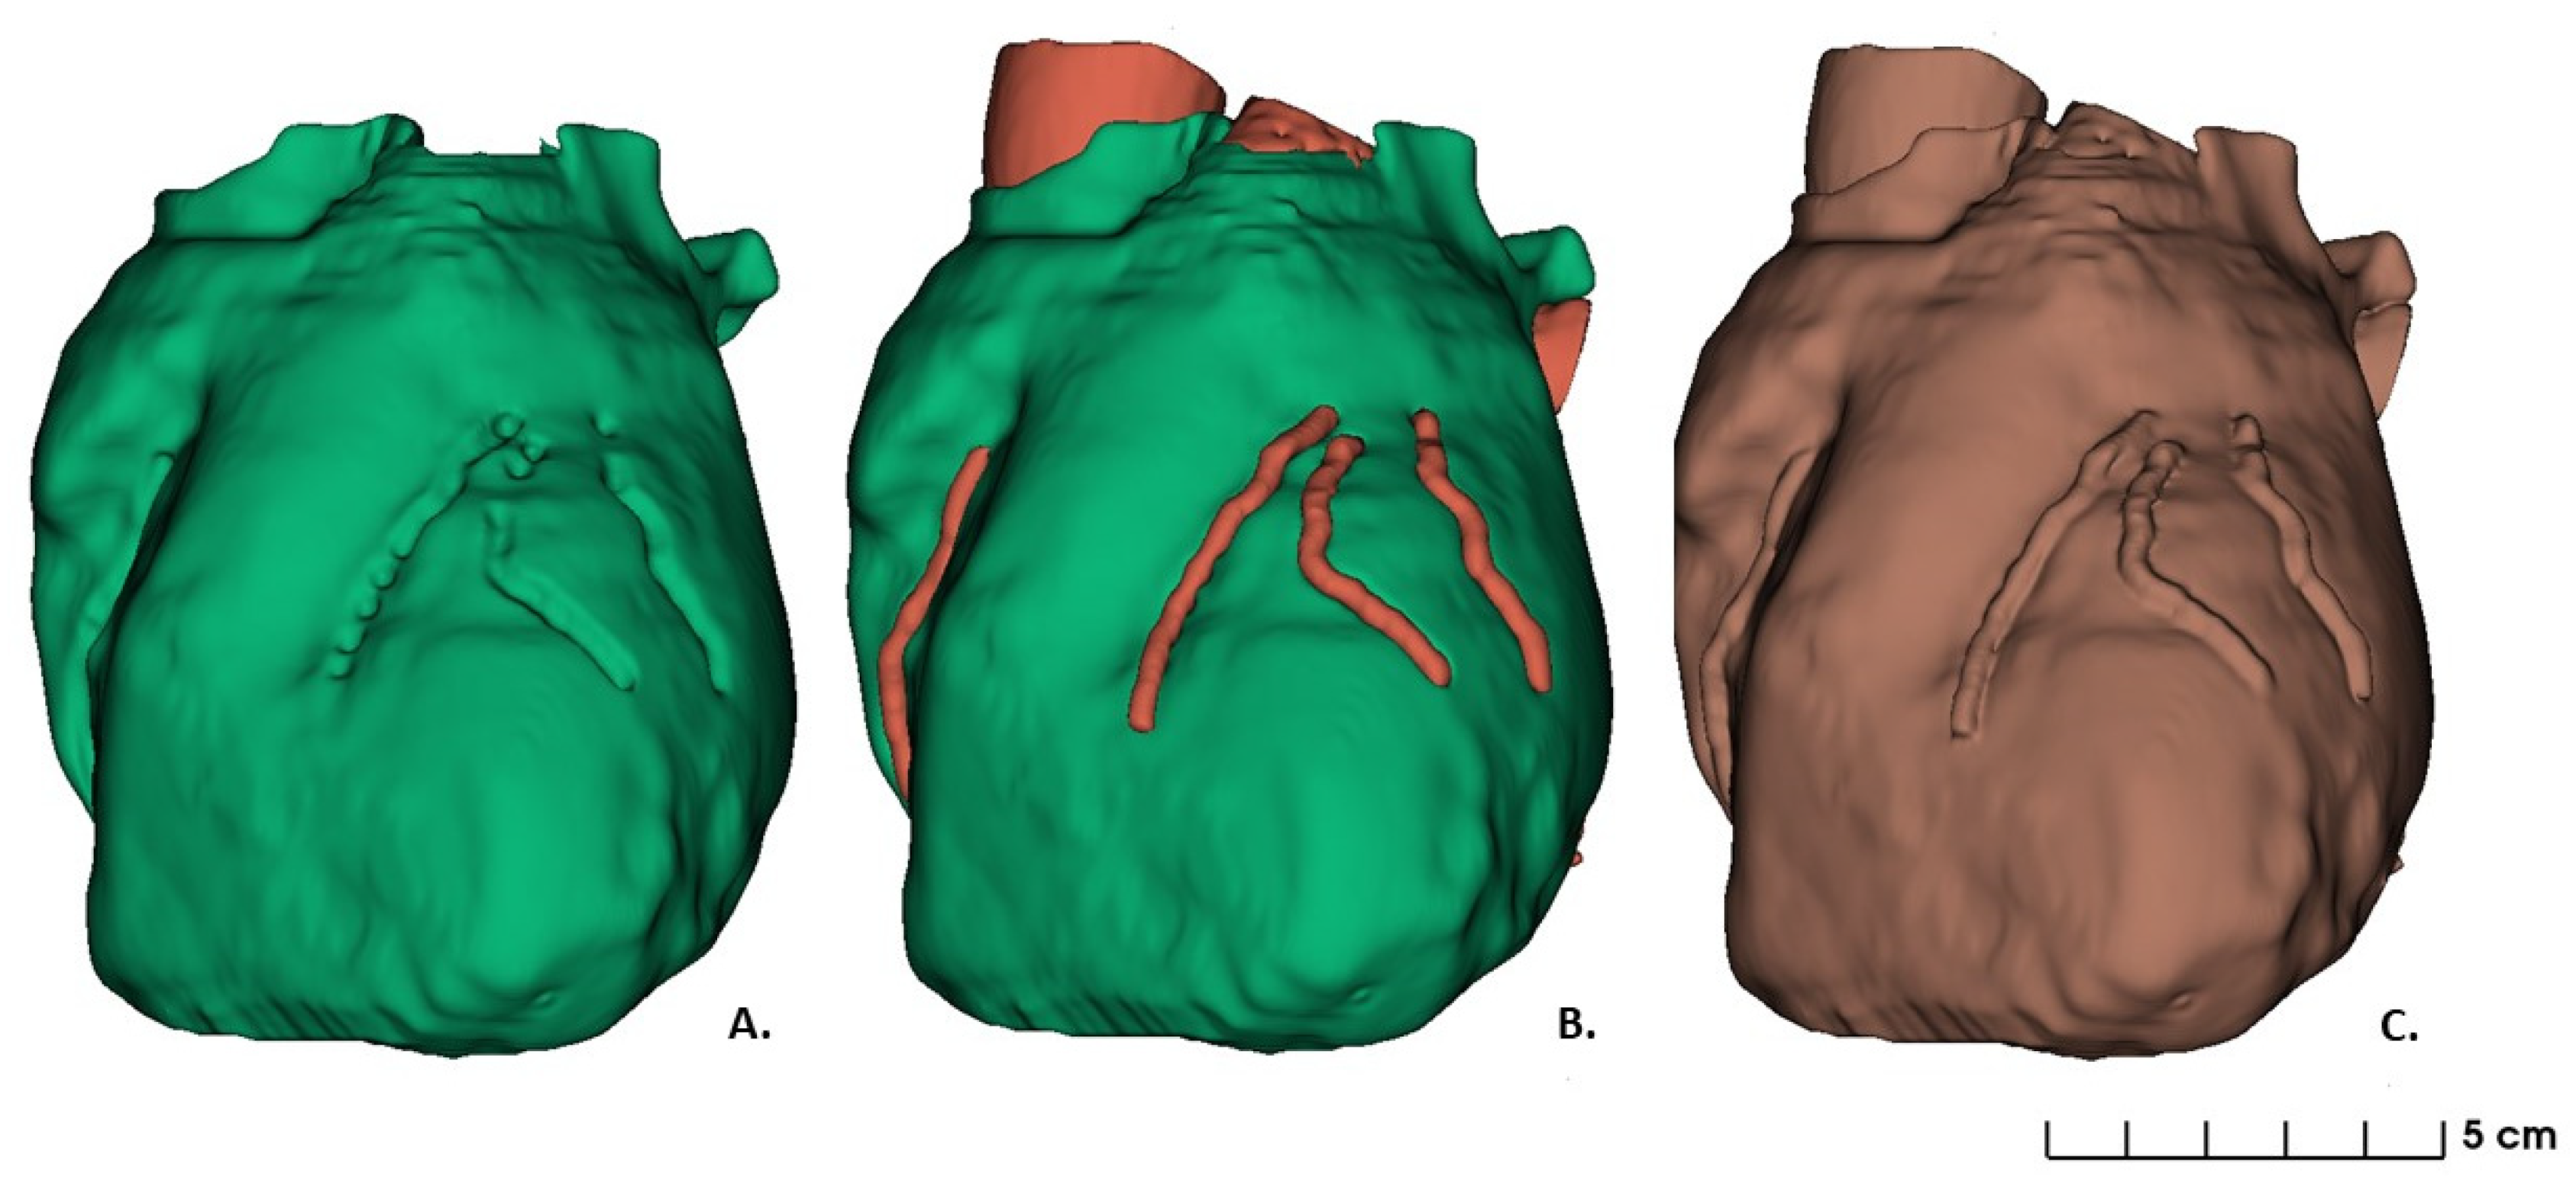

2.1. Data Acquisition and Images Segmentation: 3D Heart Model Design

3. Results